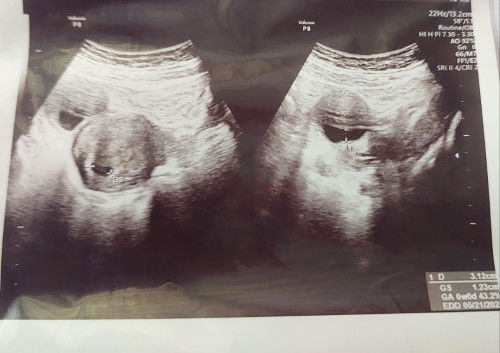

#Sharing_dong_Bund jadi bulan mei sebelum hamil tu udah pernah usg dan rahim bersih tanpa kista. Nah hari ini ke obgyn mau memastikan kehamilan dan letaknya. Menurut usg udah 6week, baru kantongnya aja yg ada. Tapi ada kista 3.1cm. Kata dokter gapapa karena bisa jd faktor hormon kehamilannya yg menyebabkan ada kista. Nah di sini ada yg sama juga ga ya bund? Selanjutnya apakah semakin besar kistanya atau semakin kecil ?